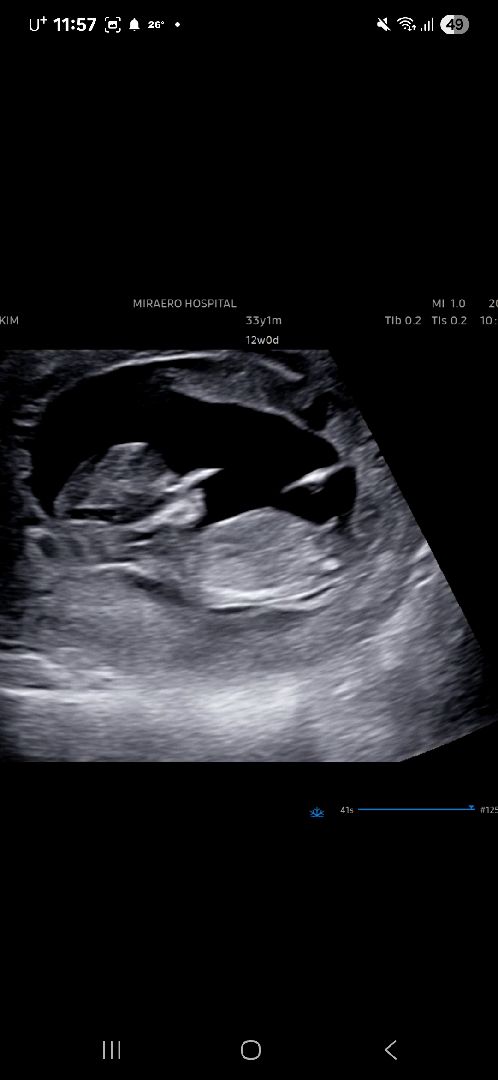

12주0일 둘째 각도법 봐주세요🥹

둘째 성별이 궁금해요~!! 고수님들 투표 부탁드려요🫶🫶

아들같은데용!!!!

자매맘을 원했는데 아들인가봐여ㅠ🥲